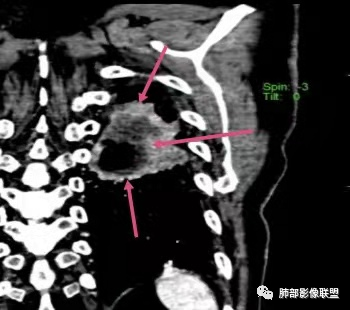

双肺多发结节影,树芽征,小叶中心分布,左肺下叶不规则空洞,洞内壁光滑,见液平,洞壁似与支气管相通,增强扫描明显强化,可见血管造影征。三周左右复查空洞明显缩小。

首先双肺多灶多形态病灶,考虑结核,聚焦左下肺病灶,空洞,内壁尚光整,有明显液化坏死,增强无明显强化,壁内可见支气管充气征,复查后空洞缩小,首先考虑良性,结核伴脓肿,鉴别鳞癌

胸部CT:双肺多发小斑片、树芽、索条灶,左下肺大片不均质实变,远肺门侧厚壁空洞,气液平,内壁有坏死物残留,增强可空洞壁不均匀强化,近端支气管壁不规则增厚堵塞,实变影内可见与洞壁平行支气管。抗炎3周有缩小。

3.注意到左肺下叶空洞性病灶,腔壁厚度不均,环形强化较为明显,壁间支气管血管影走行,腔内液气平面,这通常见于感染性病灶,如脓肿,经治疗病灶吸收也高度支持病灶主体成分为脓肿。

4.老年男性患者,痰中带血,体重减轻,空洞性病灶壁厚不均疑及肿瘤性病变符合常理。

尽管坏死明显,但穿行血管结构自然,血供如此丰富,鳞癌的判断使人望而却步,腺癌的判断也缺乏有说服力的线索。